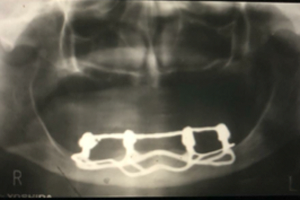

Figuras 3 e 4 – Infraestrutura metálica pronta e radiografia final do caso concluído.

Figuras 5 e 6 – Aspecto clínico e radiográfico de reabilitação com implantes osseointegrados superiores e subperiósteos (justaósseos) inferiores. Estes com 30 anos de função.

Figuras 7 e 8 – Controle clínico e radiográfico de 10 anos da nova reabilitação implantossuportada realizada pelo Dr. Sérgio Jayme, usando os mesmos implantes justaósseos inferiores realizados pelo Dr. Nilton De Bortoli, 40 anos antes.